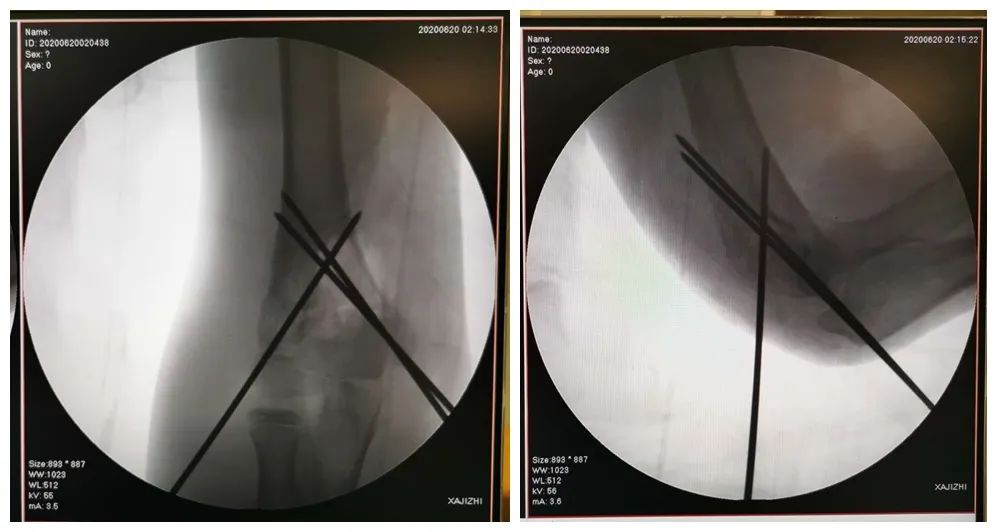

术中解除血管神经卡压并修复挫断神经,桡动脉恢复搏动。手法复位肱骨髁上骨折断端,在术中C臂导航下进行精准克氏针固定,骨折断端近解剖复位,逐层缝合术区切口,石膏托固定。凌晨2点40分,手术结束。